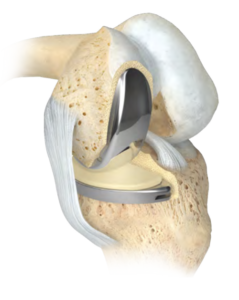

Operative Therapie: Teilendoprothese des Kniegelenkes

Bei einer isolierten Arthrose auf der Innen- oder Aussenseite sowie des Gleitlagers der Kniescheibe des Kniegelenkes ist es möglich nur den betroffenen Anteil des Gelenkes zu ersetzen. Hierbei werden hochwertige Titanimplantate entsprechend der benötigten Größe an den Ober- und Unterschenkel angepasst. Die Meniskusfunktion wird durch einen Platzhalter aus hochvernetztem Polyethylen übernommen. Die Implantation einer Schlittenprothese stellt somit ein sehr gewebeschonendes Verfahren dar, bei welchem die kniegelenksstabilisierenden Bänder erhalten werden. Somit kann eine exakte Wiederherstellung des ursprünglich gesunden Kniegelenkes erreicht werden. Das bedeutet für den Patienten das Erreichen einer Schmerzfreiheit und eines vollen Bewegungsumfanges innerhalb kürzester Zeit. Der Zugang wird hier jeweils minimalinvasiv über dem arthrotischen Abschnitt des Gelenkes gewählt. Wir achten hier speziell darauf die anderen Anteile des Gelenkes in Ihrem Originalzustand zu belassen sodass bereits am Tag der Operation alle Patienten mit Bewegungsübungen beginnen und Ihr neues Kniegelenk mit Unterstützung belasten können.

Operative Therapie: Komplette Endoprothese des Kniegelenkes

Eine fortgeschrittene Arthrose, welche alle Anteile des Kniegelenkes betrifft, kann nur noch durch den Ersatz der kompletten Oberfläche therapiert werden. Somit können auch entstandene Achsfehler und Beinlängendifferenzen ausgeglichen, Knochendefekte aufgefüllt und die Funktion dauerhaft geschädigter Bänder ersetzt werden. Hierbei sollte darauf geachtet werden, für jeden Patienten das individuell benötigte System einer Totalendoprothese herauszufinden. So gibt es nicht nur Unterschiede zwischen Mann und Frau sondern auch in der Bandstabilität und in der bereits angesprochenen Beinachse. Somit kann gewährleistet werden, dass bei jeder Operation die bestehende Anatomie respektiert und eine optimale Funktion wiederhergestellt wird. Die von uns verwendeten Prothesenteile sind hochmodern beschichtete, bestehen aus Edelmetallen und ermöglichen ein hohes Mass an Beugefähigkeit des Gelenkes. Als Meniskusersatz benutzen wir einen hochvernetzen Kunststoff welcher als zusätzlichen Schutz noch mit Vitamin E angereichert ist.

Auch können wir in geeigneten Fällen auf den Massanzug des Kniegelenkes, dem künstlichen Gelenk aus dem 3D-Drucker zurückgreifen. Hierbei wird individuell für Ihr Knie ein Oberflächenersatz hergestellt. Die Operation kann sowohl in Teil- als auch in Vollnarkose durchgeführt werden. Aufgrund unsere Philosophie erhalten sie eine speziellen, mit den Anästhesisten abgestimmte Schmerztherapie Der Zugang zum Kniegelenk erfolgt mit nur einem Hautschnitt. Dann wird die verschlissene Gelenkoberfläche sparsam entfernt und Überstände abgetragen. Anschließend wird die neue Gelenkoberfläche geschlechts- und größenspezifisch an den Knochen angepasst. Den Eingriff führen wir ohne sogenannte Blutsperre durch. Dies bedeutet, dass zu jedem Zeitpunkt der OP Ihr Gewebe optimal mit Blut und Sauerstoff versorgt ist. Die Verbindung der Prothesenkomponenten wird durch einen speziellen zementähnlichen Verbundstoff gesichert. Er ist in Minutenschnelle ausgehärtet, so dass das Kunstgelenk umgehend im Knochen verankert ist. Bei der gesamten Operation bleiben die wichtigen Bänder des Kniegelenkes erhalten, so dass dem Knie auch nach der Operation noch die physiologische Stabilität und die Beweglichkeit erhalten bleibt.